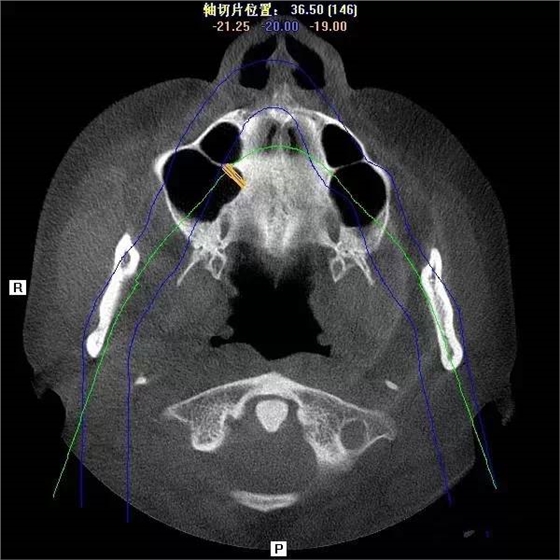

第一圖、臨床上最常見的上頜竇類型之一(高度稍顯不足、上頜竇內(nèi)干凈,提示做上頜竇內(nèi)提升即可)